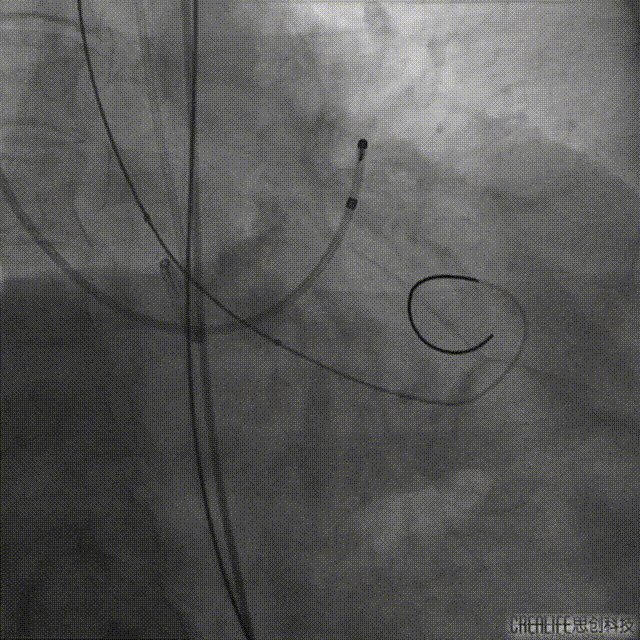

预装TaurusEliteAV23瓣膜,输送系统顺利过弓、跨瓣,初始于瓣环平面下2mm精准定位释放,释放过程中瓣膜锚定出现下滑。

瓣膜定位

瓣膜释放下滑

予以完全回收瓣膜后,将瓣膜重新定位于瓣环平面0mm精准定位释放。

瓣膜再次定位

瓣膜释放后流入端形态稍受限伴少量反流,予以20mm球囊后扩张瓣膜形态、位置良好,冠脉血流灌注正常,弓部造影未见异常。

球囊后扩

后扩后造影